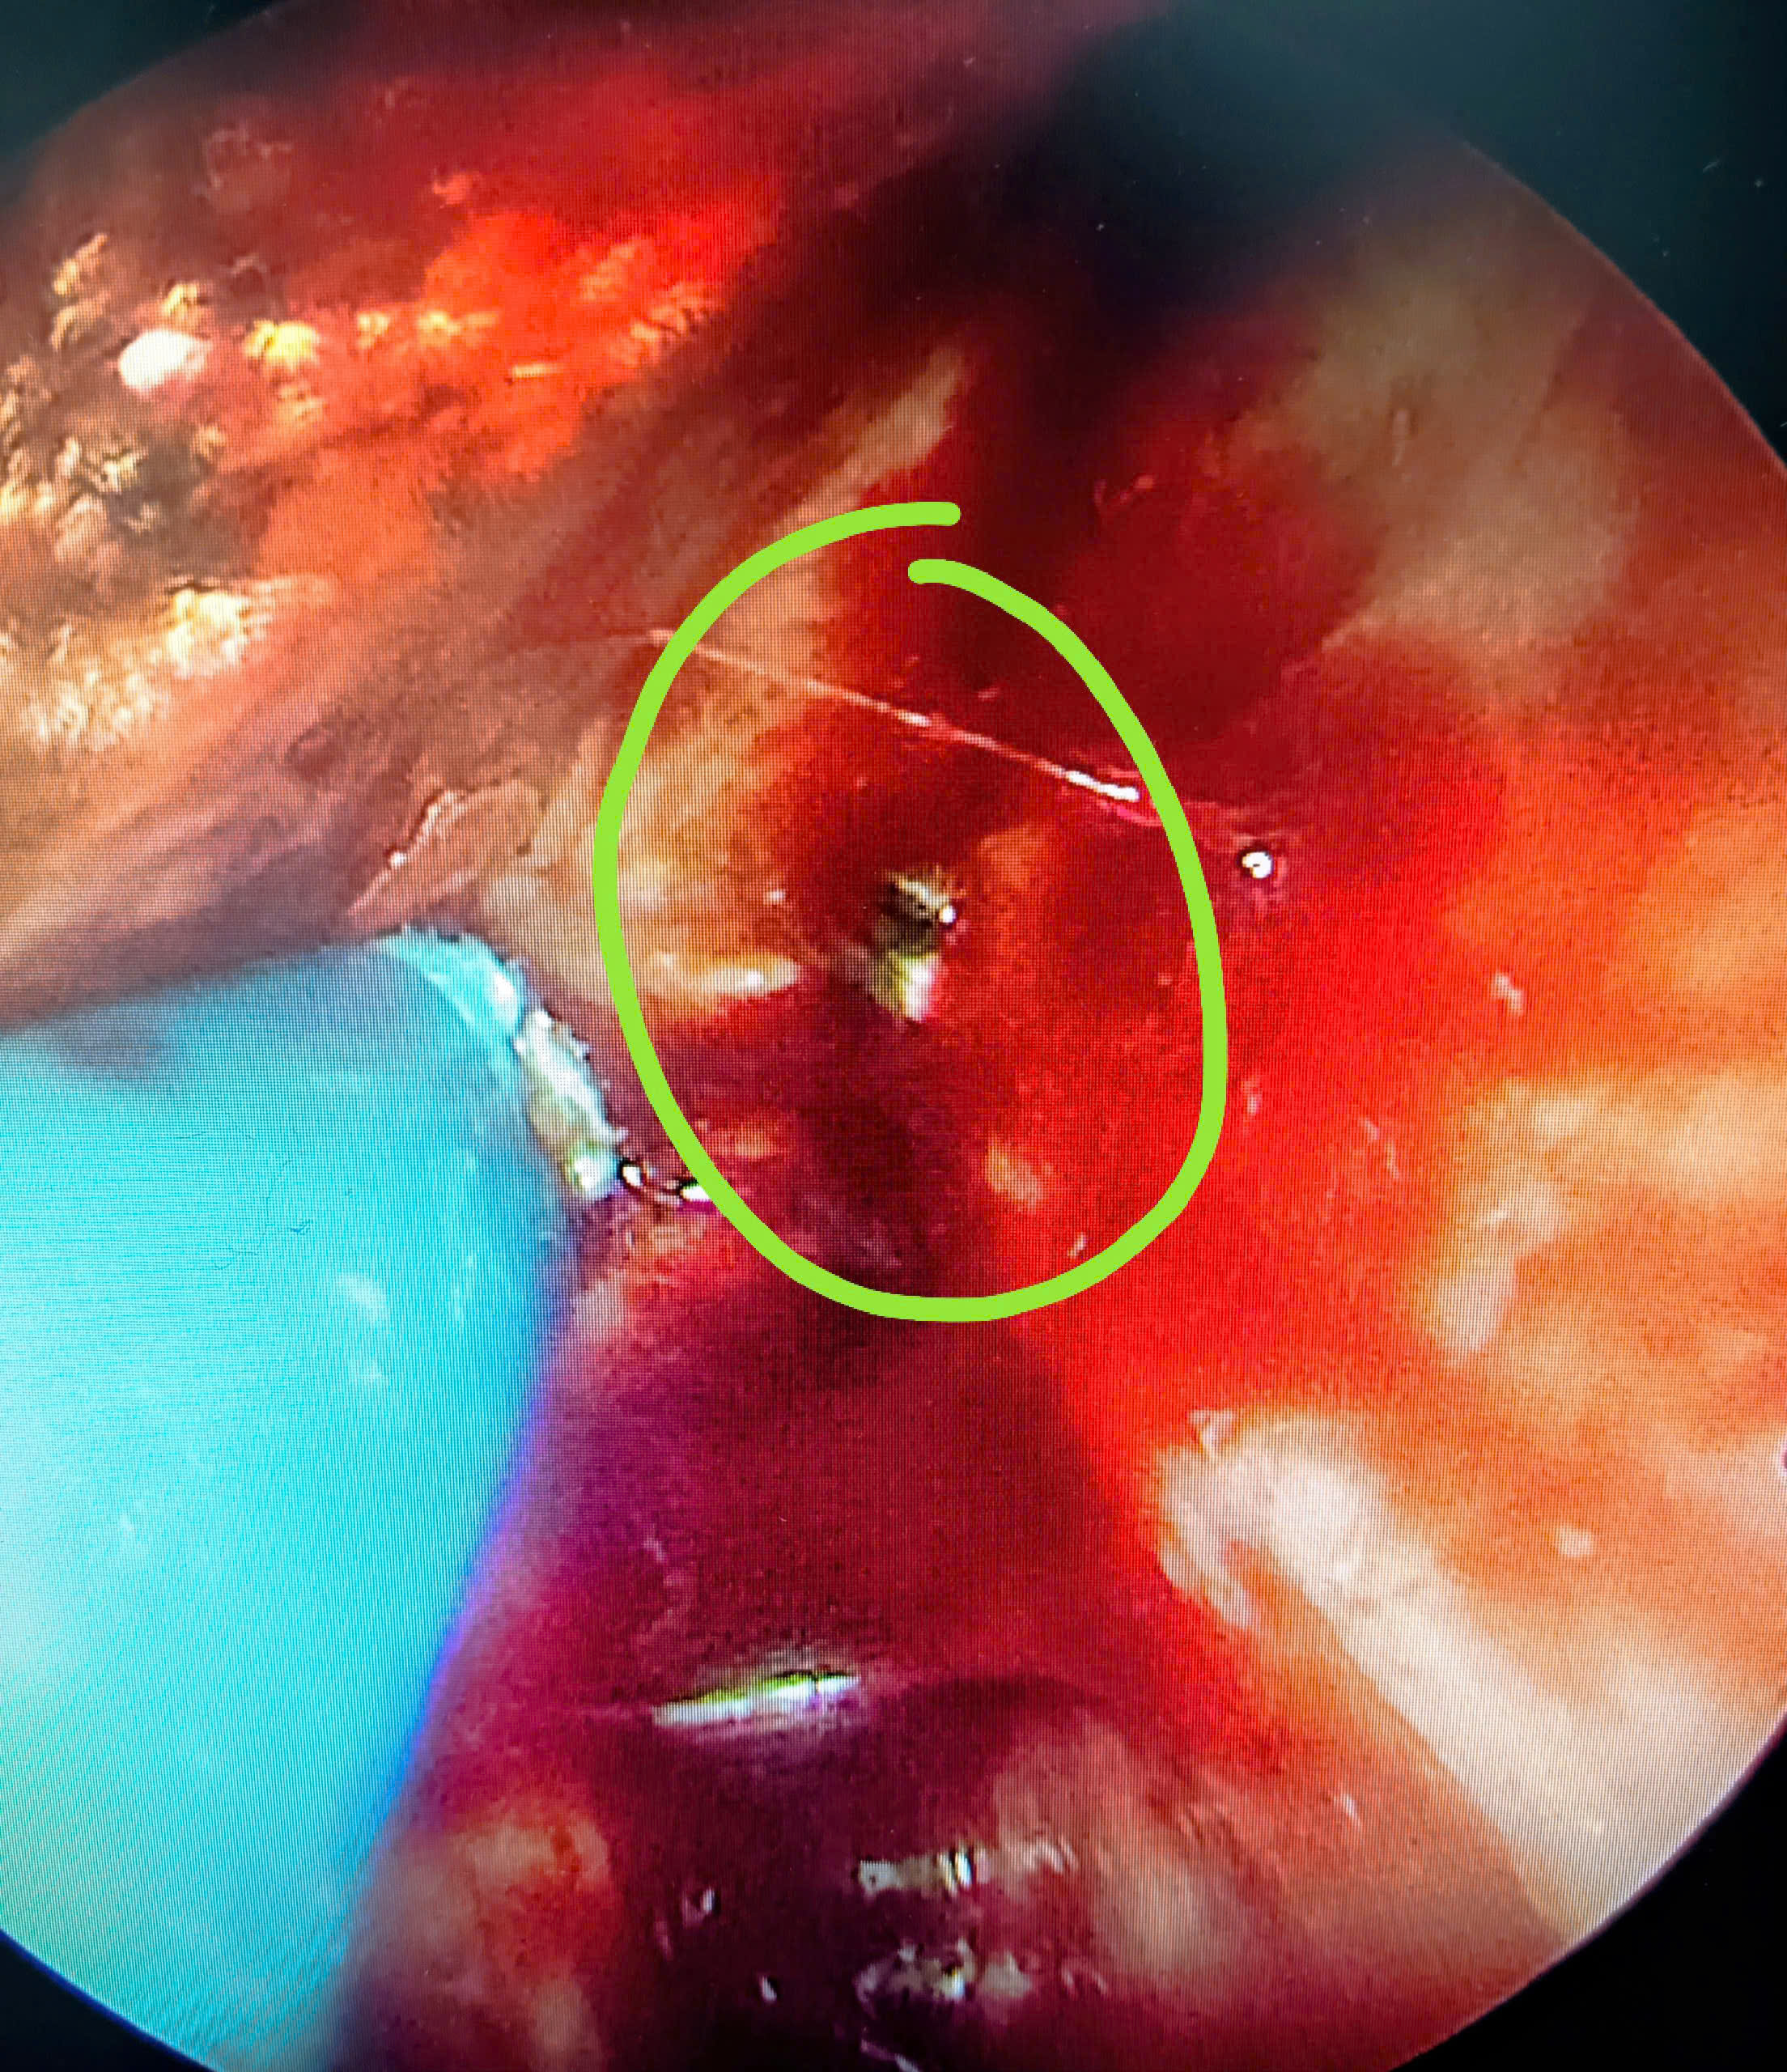

Tại lần thăm khám này, bệnh nhân được chỉ định nội soi Tai Mũi Họng kết hợp chụp cắt lớp vi tính (CLVT) xoang. Kết quả nội soi cho thấy vách ngăn mũi bị thủng, niêm mạc có những biến đổi viêm mạn tính. Đặc biệt, hình ảnh CLVT phát hiện dị vật cản quang nằm ở phần sau – trên của vách ngăn mũi phải, cách cửa mũi trước khoảng 7 cm, sát mặt trước xoang bướm.

Trong quá trình phẫu thuật, các bác sĩ đã lấy ra thành công dị vật tồn dư, nhiều khả năng là mảnh dụng cụ phẫu thuật bị gãy từ ca mổ năm 1984. Dị vật nằm sâu, sát vùng trước xoang bướm – vị trí khó tiếp cận, lý giải vì sao các lần phẫu thuật trước đó không phát hiện được.